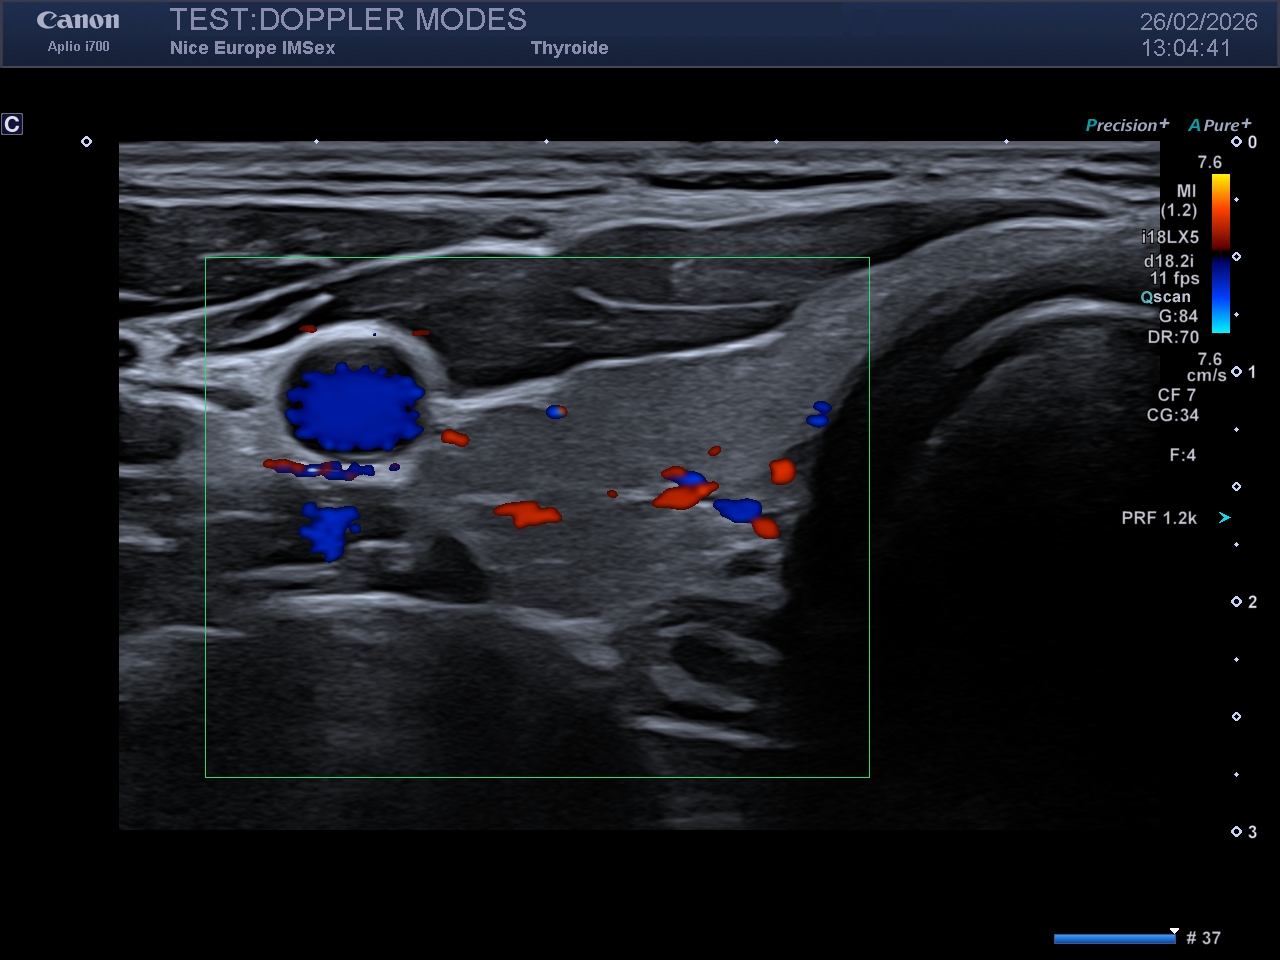

Le Doppler couleur est conçu pour cartographier la vitesse moyenne et la direction du flux sanguin. Il traduit ces informations en une carte de couleur qui se superposera à l'image échographique "mode B" (en nuances de gris).

Sur un réglage dit "usine", ou par défaut :

- le flux rouge se rapproche de la sonde

- le flux bleu s'éloigne de la sonde

Ce mode est idéal pour évaluer les directions et les vitesses relatives de circulation des flux. Il est par contre très peu utile pour les fluxs lents, en raison de filtres empêchant leur visualisation et est très dépendant à de nombreux réglages (cf ci après, section Professeur), notamment un point crucial et capital : l'effet Doppler est nul, donc non mesurable, lorsque l'angle d'observation est de 90°.

Légende : Image en Doppler couleur d'un rein droit

Le Doppler couleur repose sur le traitement du signal par autocorrélation. Il n'analyse pas l'ensemble du spectre des vitesses, mais estime la vitesse moyenne et la variance (dispersion des vitesses) au sein d'un volume d'échantillonnage.

Ces informations quantitatives sont codées chromatiquement et superposées à l'imagerie morphologique en mode B. Par défaut (réglages d'usine), la convention chromatique est généralement la suivante :

Rouge : Flux se dirigeant vers la sonde (décalage de fréquence positif).

Bleu : Flux s'éloignant de la sonde (décalage de fréquence négatif).

Une règle d'or d'interprétation : Il est impératif de souligner que cette colorisation est purement arbitraire et modifiable à tout instant par l'opérateur (inversion de la carte couleur). Par conséquent, la vérification systématique de l'échelle couleur (la barre colorimétrique affichée en marge de l'écran) doit être un réflexe absolu et incontournable avant toute conclusion hémodynamique directionnelle.

Idéal pour cartographier les directions, repérer les turbulences et estimer les vitesses de circulation, le CDI présente des limites inhérentes à sa physique. Il est strictement dépendant de l'angle d'insonation THETA. Si le faisceau est perpendiculaire au vaisseau (cos(90°) = 0) aucun flux n'est détecté. De plus, il est soumis à la limite de Nyquist ; un réglage inadapté de l'échelle des vitesses entraîne un phénomène de repliement spectral (aliasing), traduisant faussement une inversion de flux.